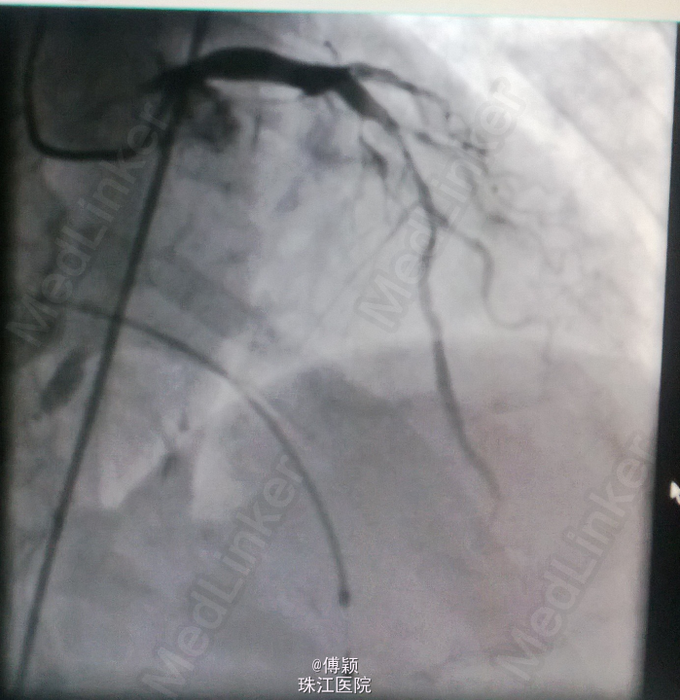

诊断:1.急性下壁心肌梗死(STEMI),心源性休克,心功能IV级(killip分级);2.高血压病2级(很高危);3.2型糖尿病;4.陈旧性脑梗塞;5.高尿酸血症。 处理——收入CCU后立即转去导管室行急诊冠脉造影术,术中见右冠中段以远全部闭塞,未见侧枝循环,前降支近中段见节段性狭窄70-80%,术中经6F Thrombuster血栓抽吸导管反复多次抽吸右冠,抽出数条红色血栓,并于右冠中段病变处植入Firebird 4.0*23mm药物支架,缝合鞘管时患者心电监护提示加速性实行逸博心律(110次/分左右),5min后突发室速、室颤,立即予床边电极除颤后转位室性逸博心律(105次/分)。返回病房后夜间患者多次出现室颤,予点击除颤、胺碘酮静滴等治疗后好转。术后24h内患者出现少尿,予静脉补液(5000ml/天左右)、利尿等,患者尿量基本维持在2000ml/天。术后辅查心电图见下壁导联ST段明显回落。余予抗血小板聚集、稳定斑块等治疗。